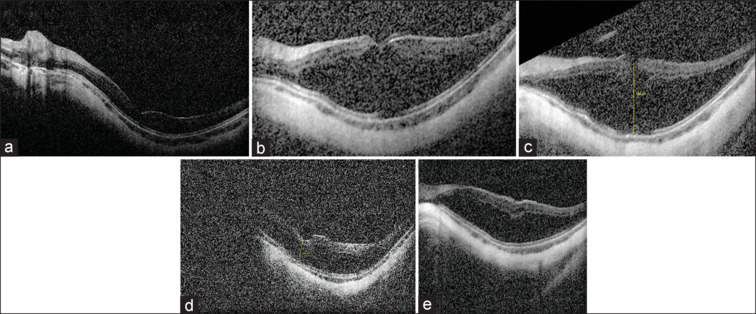

本病例报告了一名因 LRPAP1 基因同源变异而患有高度近视的儿童出现的眼窝裂伤。一名 9 岁女孩因 LRPAP1 基因同源突变而患有高度近视,右眼曾进行过视网膜脱离修复手术。裂孔病变演变为片状黄斑孔,需要进行玻璃体切除术。术后病情稳定。隐性 LRPAP1 致病变体可能会在儿童期出现近视性黄斑裂孔。需要进行长期随访,以确定早发近视眼窝沟封闭的自然史。

This case reports the development of foveoschisis in a child with high myopia due to a homozygous LRPAP1 pathogenic variant. A 9-year-old girl with high myopia due to a homozygous mutation in the LRPAP1 gene and a history of retinal detachment repair in her right eye, presented on follow-up with progressive myopic foveoschisis in the left eye noted on optical coherence tomography. The schitic changes evolved into a lamellar macular hole and required vitrectomy. Postoperatively, stabilization of the condition was achieved. Myopic foveoschisis could develop in childhood in the setting of recessive LRPAP1 pathogenic variants. Long_term follow-up is needed to determine the natural history of early-onset myopic foveoschisis.